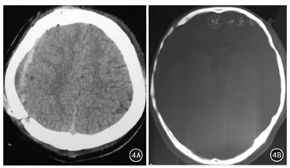

25例患者均顺利完成手术,术中无异常情况。手术时间为1.5~2.5 h,平均1.86 h。术中出血量300~450 mL,平均为320 mL。术后未出现脑脊液漏、切口感染、排异反应、自体颅骨松动凹陷、硬膜外积液等并发症。患者切口均一期甲级愈合,头颅外形均美观对称。2例患者术后出现硬膜外少量血肿,予以保守治疗方式处理,出院半月后复查CT见血肿吸收。25例患者术后均获随访,随访时间3~12个月,平均9.4个月。术后6例患者有头痛症状、2例患者出现癫痫症状,均予对症处理后缓解。术后定期复查CT显示均有骨缝结合部骨质生长,有骨瓣内板及板障骨质被吸收情况,外板完好,没有影响其骨架作用。典型病例见图4。